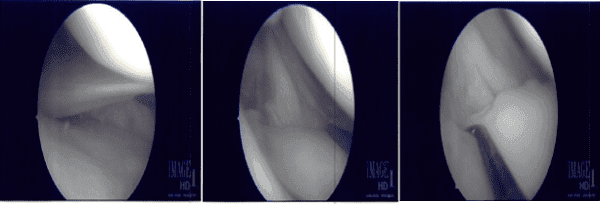

Se construyó el portal de entrada lateral y se introdujo el artroscopio. Se examinó la articulación patelofemoral y el compartimento medial y se encontró una rotura casi completa del cuerno posterior del menisco medial de la cápsula. Se tomó la decisión de repararlo.

Los márgenes se sondearon usando rasp y shamp. El menisco se acercó a la cápsula y se fijó usando FasT-Fix Nephew curvado x2. Se logró una buena oposición. Las suturas se cortaron después de la muesca. Se utilizó la técnica de todo dentro. Por último, en la zona intercondilar donde se movió el endoscopio, se encontró que el LCA estaba intacto.

El endoscopio se trasladó al compartimento lateral, donde se produjo un faying del cuerno posterior cerca de la raíz del menisco lateral. Fue desbridado con afeitadoras y ponche. El endoscopio se trasladó a la articulación patelofemoral, que se encontró en buen estado.

El desgarro meniscal lateral se desbridó aún más y se tomaron las fotos finales. Al final del procedimiento, también se utilizó micropunzón para hacer 4 o 5 agujeros en la zona intercondilar.